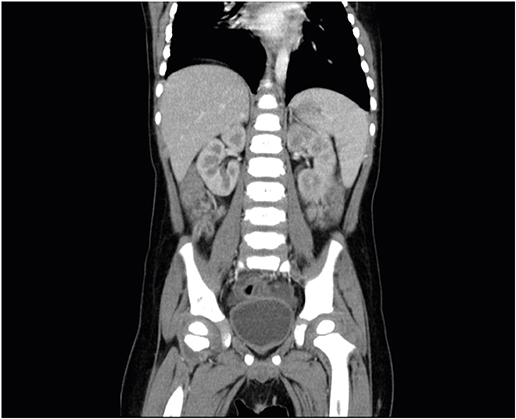

Abdominal radiography showed gaseous distension of the colon (Fig. 1). Laboratory findings included leukocytosis (22.64 k/mm3) with an upper left shift (segment 82.9%), mild anemia (12.5 g/dL), thrombocytosis (456 k/mm3) and decreased serum glucose (65 mg/dL) and sodium (134 mg/dL) levels. Plasma urea and creatinine concentrations, and those of other electrolytes were within normal limits, and C-reactive protein (CRP) was also nearly normal (0.66 mg/dL).

Fig. 1

Simple abdomen radiograph (flat) at the admission.